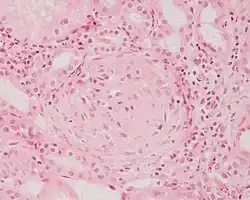

| Photomicrograph of a kidney biopsy from a person with crescentic glomerulonephritis showing prominent fibrocellular crescent formation and moderate mesangial proliferation in a glomerulus. Hematoxylin and eosin stain. | |

Rapidly progressive glomerulonephritis, also known as crescentic GN, is characterised by a rapid, progressive deterioration in kidney function. People with rapidly progressive glomerulonephritis may present with a nephritic syndrome. In management, steroid therapy is sometimes used, although the prognosis remains poor.[9] Three main subtypes are recognised:[4]: 557–558

Histopathologically, the majority of glomeruli present "crescents". Formation of crescents is initiated by passage of fibrin into the Bowman space as a result of increased permeability of glomerular basement membrane. Fibrin stimulates the proliferation of endothelial cells of Bowman capsule, and an influx of monocytes. Rapid growing and fibrosis of crescents compresses the capillary loops and decreases the Bowman space, which leads to kidney failure within weeks or months.